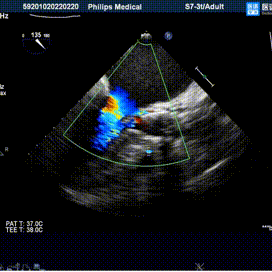

植入后评估:

植入后血流动力学改善明显